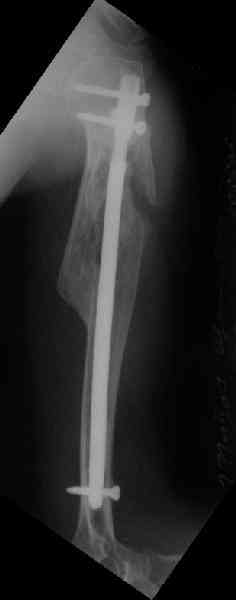

Здесь нет необходимости в серкляже. Вмешиваться на промежуточных

отломках приходится, если есть угроза перфорации кожи, или

промежуточный отломок попал в фасцию, как пуговица в петлю. В

приложении сегментарный оскольчатый перелом плеча в проксимальном

отделе, фиксированный больщеберцовым стержнем. Как видите, обошлось

без серкляжа. Функция полная.